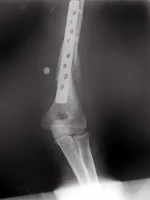

Em 1997 desenvolvi uma técnica pessoal para colocação de placas Ponte no Úmero pela via de acesso posterior, essa foi uma técnica pioneira e não começo outra cirurgião que realizasse esse tipo de técnica em 1997. 5 anos após iniciar a técnica publiquei os resultados num Poster no Congresso Brasileiro de Ombro e Cotovelo em 30 de maio a 01 de junho de 2002. Belo Horizonte – MG. Abaixo as fotos de um dos casos, esse caso foi operado em 1999 e a radiografia com resultado final em Maio de 2002.

| AP pós op Imediato |